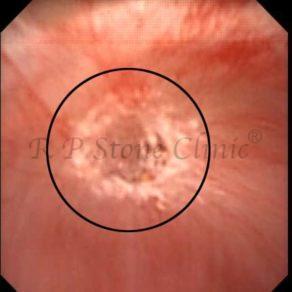

These images are taken as snap shots from the video recording of RIRS Surgery done at our hospital. These are Randall’s Plaques seen with Digital FLEX XC & Digital FLEX XC S. The cream or whitish patches are seen on the tips of RENAL PAPILLAE as seen in images below.

The Below Images Show Small Stones attached to the Renal Papillae.